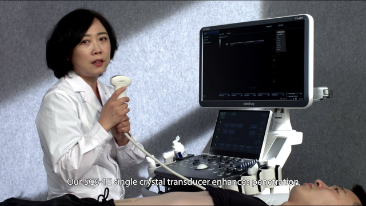

Die St?rken des Resona 7 sind bis ins kleinste Detail durchdacht. Seine erstklassige Bildqualit?t ist das Ergebnis einer erfolgreichen Fusion. Mindray und Zonare Medical Systems haben ihren Kernkompetenzen geb├╝ndelt, um ein Premiumsystem Wirklichkeit werden zu lassen. Dank der Vector Flow-Funktion k?nnen bei Gef??untersuchungen mehr als 400 Bilder pro Sekunde dargestellt werden. Somit entstehen ganz neue M?glichkeiten der Diagnose.

Der hochaufl?sende 21,5 Zoll gro?e LED-Monitor liefert gestochen scharfe Bilder und ideale Rahmenbedingungen. Der in der Neigung verstellbare Touchscreen l?sst sich ganz leicht bedienen und auf die jeweiligen Bedingungen der klinischen Umgebung anpassen.

Dank der ZONE Sonography?-Technologie (ZST+) wird das B-Bild des Resona 7 ├╝ber die komplette Tiefe fokussiert, sodass keine Fokuspunkte mehr gesetzt werden m├╝ssen. Die Schall-Lauf-Geschwindigkeit (SSC) wird auf Knopfdruck individuell auf den Patienten angepasst, was die Darstellung von Organen, Grenzfl?chen und Gewebever?nderungen erheblich verbessert. Und dank der fortschrittlichen iFusion-Funktion k?nnen optional die Daten von Ultraschall-, MRT-und CT-Bildern synchronisiert werden.